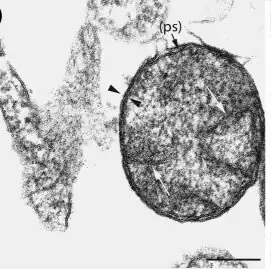

Rickettsia helvetica,[2] previously known as the Swiss agent, is a bacterium found in Dermacentor reticulatus and other ticks, which has been implicated as a suspected but unconfirmed human pathogen.[3][4][5] First recognized in 1979 in Ixodes ricinus ticks in Switzerland (hence the designation helvetica) as a new member of the spotted fever group of Rickettsia, the R. helvetica bacterium was eventually isolated in 1993.[6] Although R. helvetica was initially thought to be harmless in humans and many animal species, some individual case reports suggest that it may be capable of causing a nonspecific fever in humans.[4][5][7] In 1997, a man living in eastern France seroconverted to Rickettsia 4 weeks after onset of an unexplained febrile illness.[8] In 2010, a case report indicated that tick-borne R. helvetica can also cause meningitis in humans.[9]